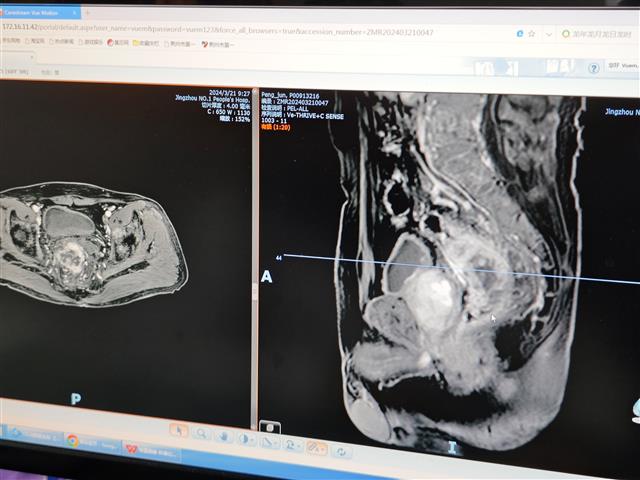

淋巴瘤也就是淋巴癌,是起源于淋巴造血系统的恶性肿瘤。当淋巴细胞发生了恶变,不受控制的生长,就会得淋巴瘤。这些淋巴瘤细胞等于是人体免疫系统的“叛军”,随着淋巴系统全身跑,四处破坏。作为发病率增长速度最快的恶性肿瘤之一,淋巴瘤在总体癌症发病中位居第八。

淋巴瘤的发病原因并不明确,某些感染、免疫、物理、化学因素及遗传等可能是潜致病因素。淋巴瘤并非不治之症,目前有很多治疗方法,治疗时需遵循“量体裁衣”个性化治疗。

荆州一医肿瘤八病区主任、副主任医师 张为家:淋巴瘤比实体瘤、肝癌、肺癌的治疗效果会好很多,最常见的淋巴瘤治愈率是60%,早期的淋巴瘤是有希望治愈的,它的治疗方法是非常多的,除了放化疗、靶向治疗,还有CAR-T目前比较火热,总体而言5年治愈率还是非常高的,即使是晚期也还是有希望治愈的。